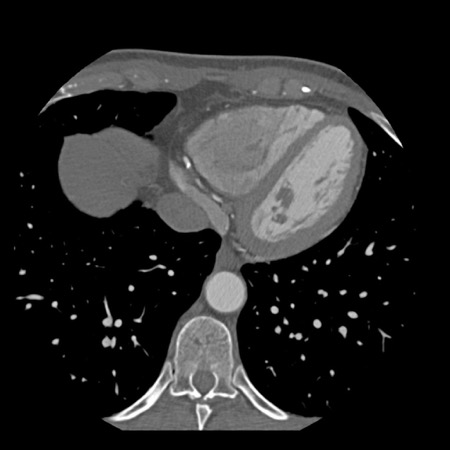

case 1 – CAD-RADS 2/P1

First, scroll through the scan.

Not all images are included. Some images without any abnormalities are skipped

from the series.

How would you describe the findings on the coronary CTA?

The findings are:

- Agatston score of

this patient was 14 (P1). Please, also note the calcification of the aortic valve. - Some partially

calcified and calcified plaques are present in the LAD with mild stenosis

(25-49%). - Calcified-plaque in

the LCX causing minimal stenosis (<25%). - Non-calcified

plaque in the distal RCA causing minimal stenosis (<25%). - This patient classifies

as CAD-RADS 2/P1, which means no further workup is needed.